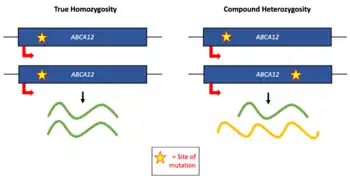

Disease causing variants in adenosine triphosphate binding cassette transporter protein (A12 gene)[3] on chromosome 2 carries information for lipid transportation to keratinocytes in the cutaneous layer. The malfunction of this gene causes scaly tight skin. The tightening of the skin pulls the eyes and lips back causing eclabium and ectropion. This disease has a Rare autosomal recessive mode of inheritance.

Also, If a mother tests positive for a mutation in the ABCA12 gene,[6] eclabium as a result of Ichthyosis can be present in the child. Ichthyosis is characterized by tight scaly skin along with ectropion which is outward turning of eyelids. If the skin is tight enough to be pulling on the eyes then it is safe to diagnose that the tight skin is also pulling on the lips making them turn outward

To prevent eclabium, testing for the mutation for ABCA12 gene can be done on the mother to see if the unborn child has the gene. This allows the parents to make a decision accordingly because most children with ABCA12 gene mutation[6] will have eclabium.

Eclabium caused by harlequin ichthyosis is more severe. Its prognosis is very poor.[9] Most affected babies do not survive the first week of life. Survival rates based on the severity of the case have varied from 10 months to 25 years with supportive treatment. The oldest person in the united states with Harlequin Ichthyosis is 23 year old Stephanie Turner.[10] She was also the first person to have a child with this condition. She has two children and neither have the condition. There is a 25% chance of this condition reoccurring in the mothers next pregnancy. Genetic counseling is highly recommended for couples who have the mutated ABCA12 gene.